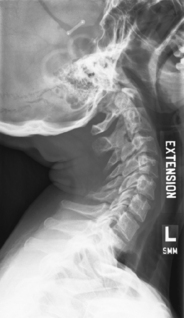

Lateral hyperflexion and hyperextension (S)

Hyperflexion and hyperextension critique